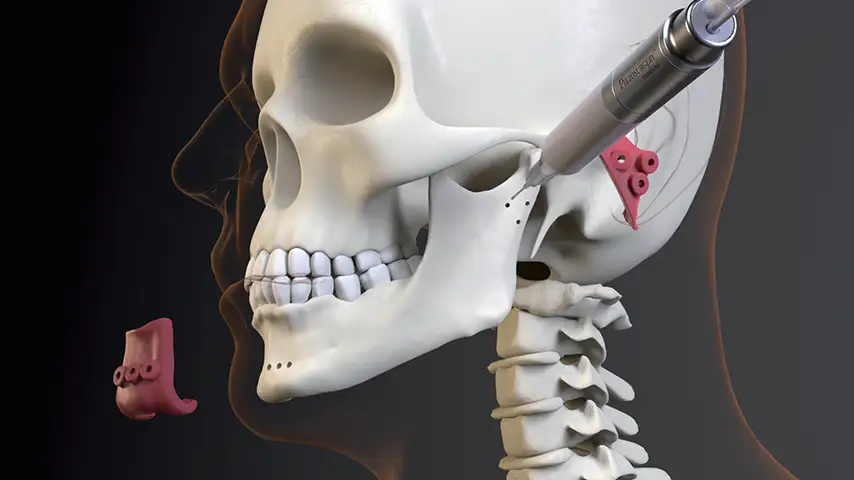

Selective osteotomies, safety on soft tissues

Mandibulotomy and mandibulectomy / maxillectomy

Osteotomies for harvesting and remodelling